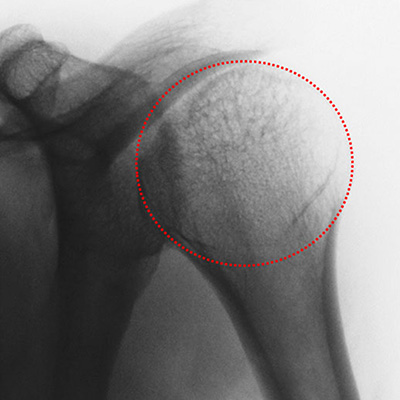

Rx. Antero-Posterior: típica imagen de luxación posterior (Fig. 1).

Figura 1: Rx. A.P. Hombro Izquierdo: Imagen en luna llena características de luxación posterior.